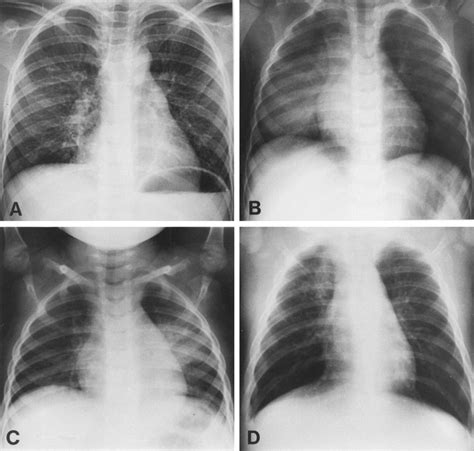

A Pneumonia X-ray is a medical imaging test that uses electromagnetic radiation to create pictures of the inside of your chest. When you have pneumonia, the air sacs (alveoli) in your lungs can become filled with fluid or pus. In an X-ray image, these filled air sacs appear as opaque, whitish patches or "opacities," which stand out against the dark, air-filled healthy lung tissue. This visual evidence is critical for doctors to distinguish pneumonia from other conditions like bronchitis or asthma.

When a radiologist reviews a Pneumonia X-ray, they are looking for specific indicators of disease. Healthy lungs on an X-ray typically appear black because they are filled with air, which does not block the X-ray beams. Conversely, infected tissue blocks these beams, leading to white areas on the film. These findings are often referred to in clinical reports as "infiltrates" or "consolidation."

Localized white patches (Consolidation) Indicative of active pneumonia infection

Cloudy shadows Possible interstitial inflammation or fluid